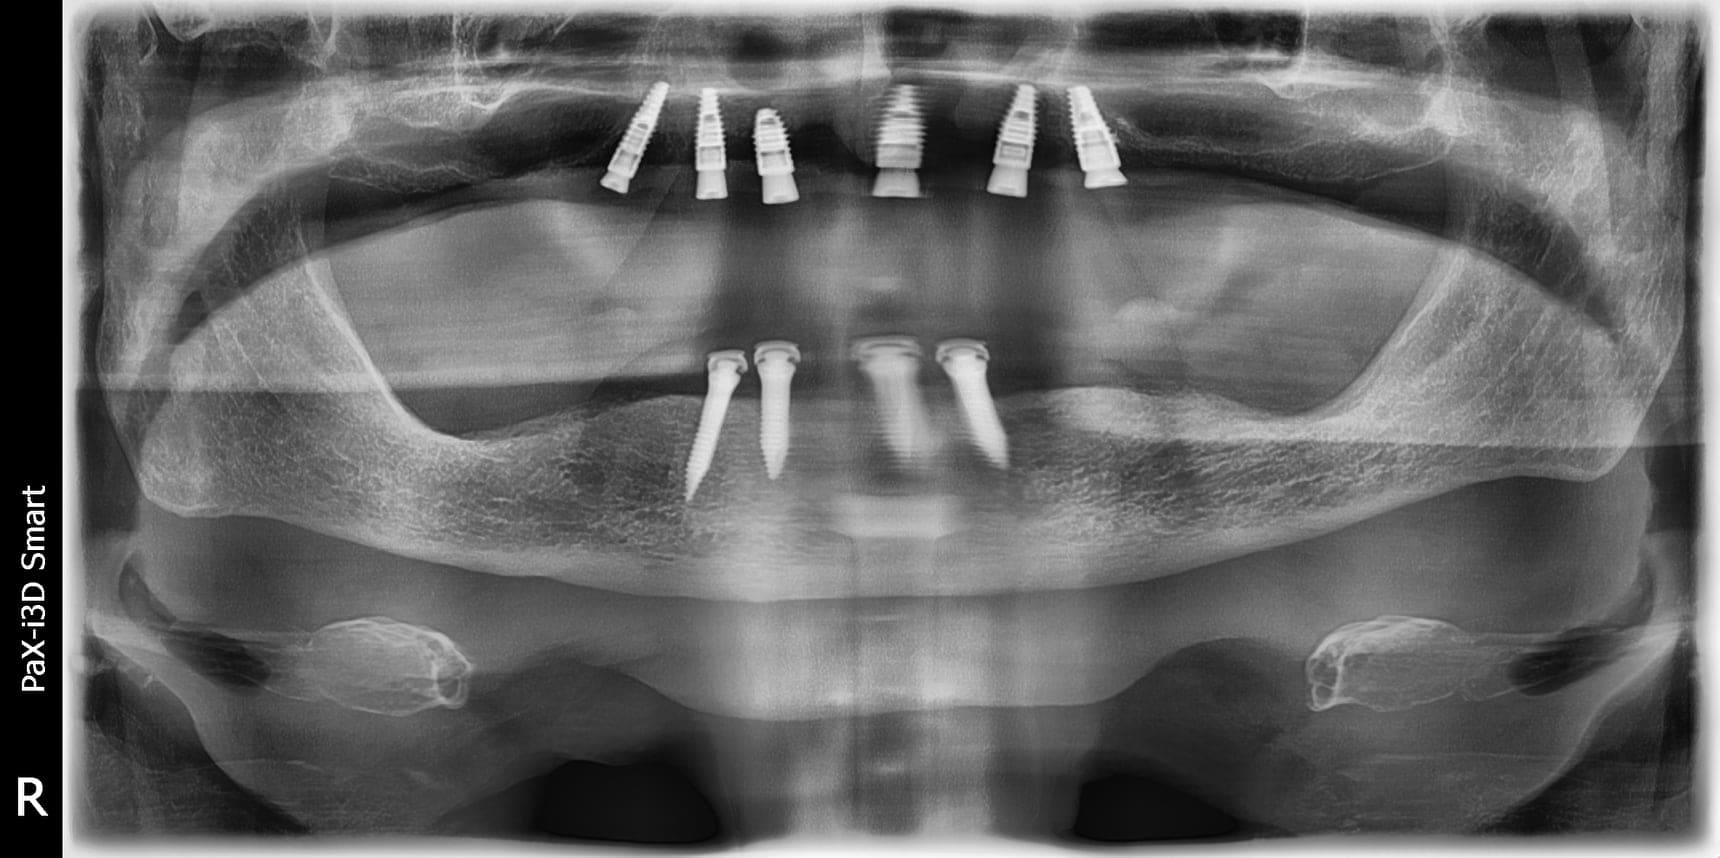

Une parution sur Facebook m'a interpelé et donnée l'idée d'ouverture du débat, en voici des photos et extrait des échanges:

X écrivait : "Bonjour à tous,

Je me lance, première publication de cas 🙂

Patient de 80 ans, bon état de santé générale, édenté complet depuis une vingtaine d'année. Il décide qu'il en a marre que ses prothèses bougent quand il parle, surtout la mandibulaire, donc 2019 on met 4 mini-implants pour stabiliser la prothèse du bas. Le patient a peu de moyens financiers et ne souhaite pas de réhabilitation fixe.

2022, il trouve que c'est très sympa que la prothèse soit fixée, il me demande donc de faire la même chose en haut, et il souhaite passer à la prothèse fixée maxillaire mais en 2023 le temps de retrouver des finances...

Pose de 6 implants Straumann SLactive maxillaires, avec guide chirurgical complet full-guided en flapless. La prothèse amovible actuelle du patient sera stabilisée sur 6 Novaloc dans 6 semaines le temps que le patient donne le feu vert pour la prothèse fixée.

Petit cas simple, mais c'était mon premier cas de complet, toutes les critiques sont les bienvenues

Ma réaction :

Alain Fernandez Scoma

Bonjour, c'est une pano mais j'ai des doutes sur la position et l'enfouissement de certains implants.

Réponse de X :

"Oui la pano est assez trompeuse notamment sur le secteur 2 , j’ai décollé très légèrement la gencive en per opératoire pour toucher mon rebord cristal avec une sonde pari afin de vérifier l’enfouissement"

Lors de l'anesthésie j'ai remarqué une modification du volume gingival qui s'estompe mais pas complètement. Dans ce cas il me semble que le guide n'était pas en place, que l'analyse du volume osseux soit perfectible (certainement un cone beam) ... une pano reste un examen qui ne peu pas avoir un contrôle de la dimension volumétrique.